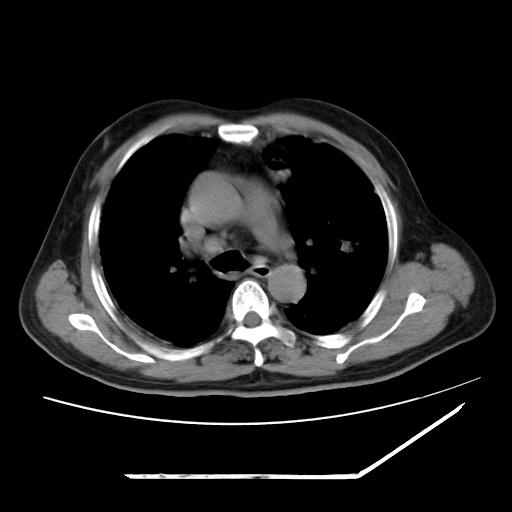

男,57,畏寒,发热

两肺野多发大小不一高密度灶,纵膈内见肿大淋巴结,要考虑转移瘤可能。双侧胸腔少量积液。

双肺多发结节样病灶,部分内见透光区,纵隔内见淋巴结肿大。结核临床如有畏寒,高热,白细胞增高首先考虑迁徙性肺脓肿(多是金黄色葡萄球菌感染)。

注意除外转移瘤。

1)考虑两肺感染性病变(金黄色葡萄球菌肺炎?);建议抗炎治疗后复查排除其他。2)双侧少量胸腔积液。